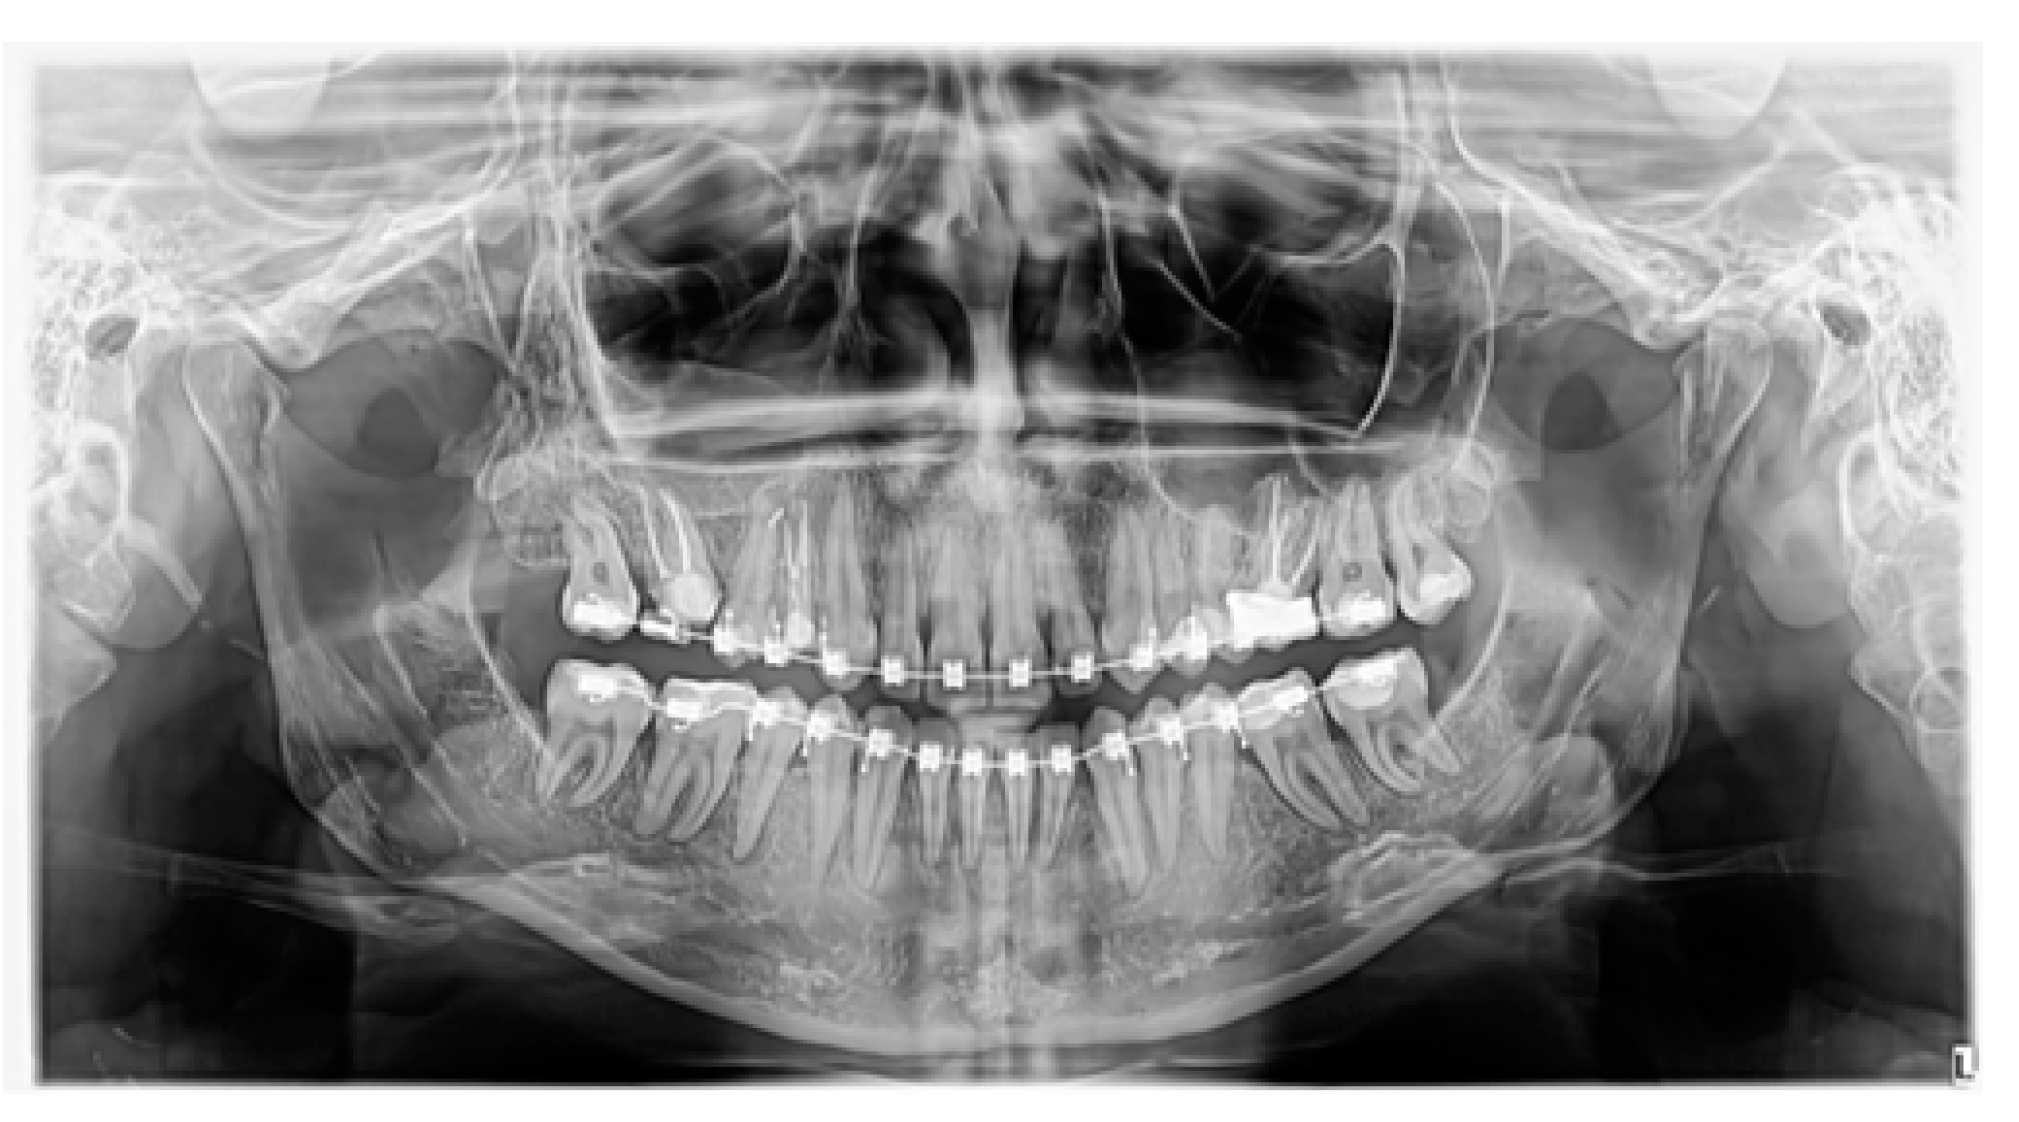

3.2. Case 2 (Figure 6, Figure 7 and Figure 8)